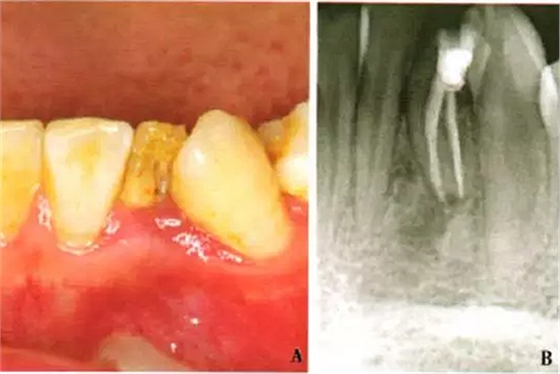

1周后,患者述疼痛消失。復(fù)診采用冷測(cè)壓方法根管充填(圖2),牙冠開髓孔處應(yīng)用Chem—flex(DentsplyDeTreyGmbH,Konstanz,Germany)充填。由于患牙牙冠形態(tài)異常,且唇側(cè)形態(tài)尚未恢復(fù);患牙周圍有牙石、軟垢,建議患者行牙周及修復(fù)治療以維持長期療效,被患者拒絕。9個(gè)月后隨訪,患者自述患牙經(jīng)治療后無癥狀,臨床檢查見32叩診正常,無松動(dòng);影像學(xué)檢查見32根尖周圍透射區(qū)域明顯減?。▓D3)。

A:32口內(nèi)像;B:X線片示32根尖周炎癥明顯減輕

圖3 左下側(cè)切牙9個(gè)月隨訪檢查